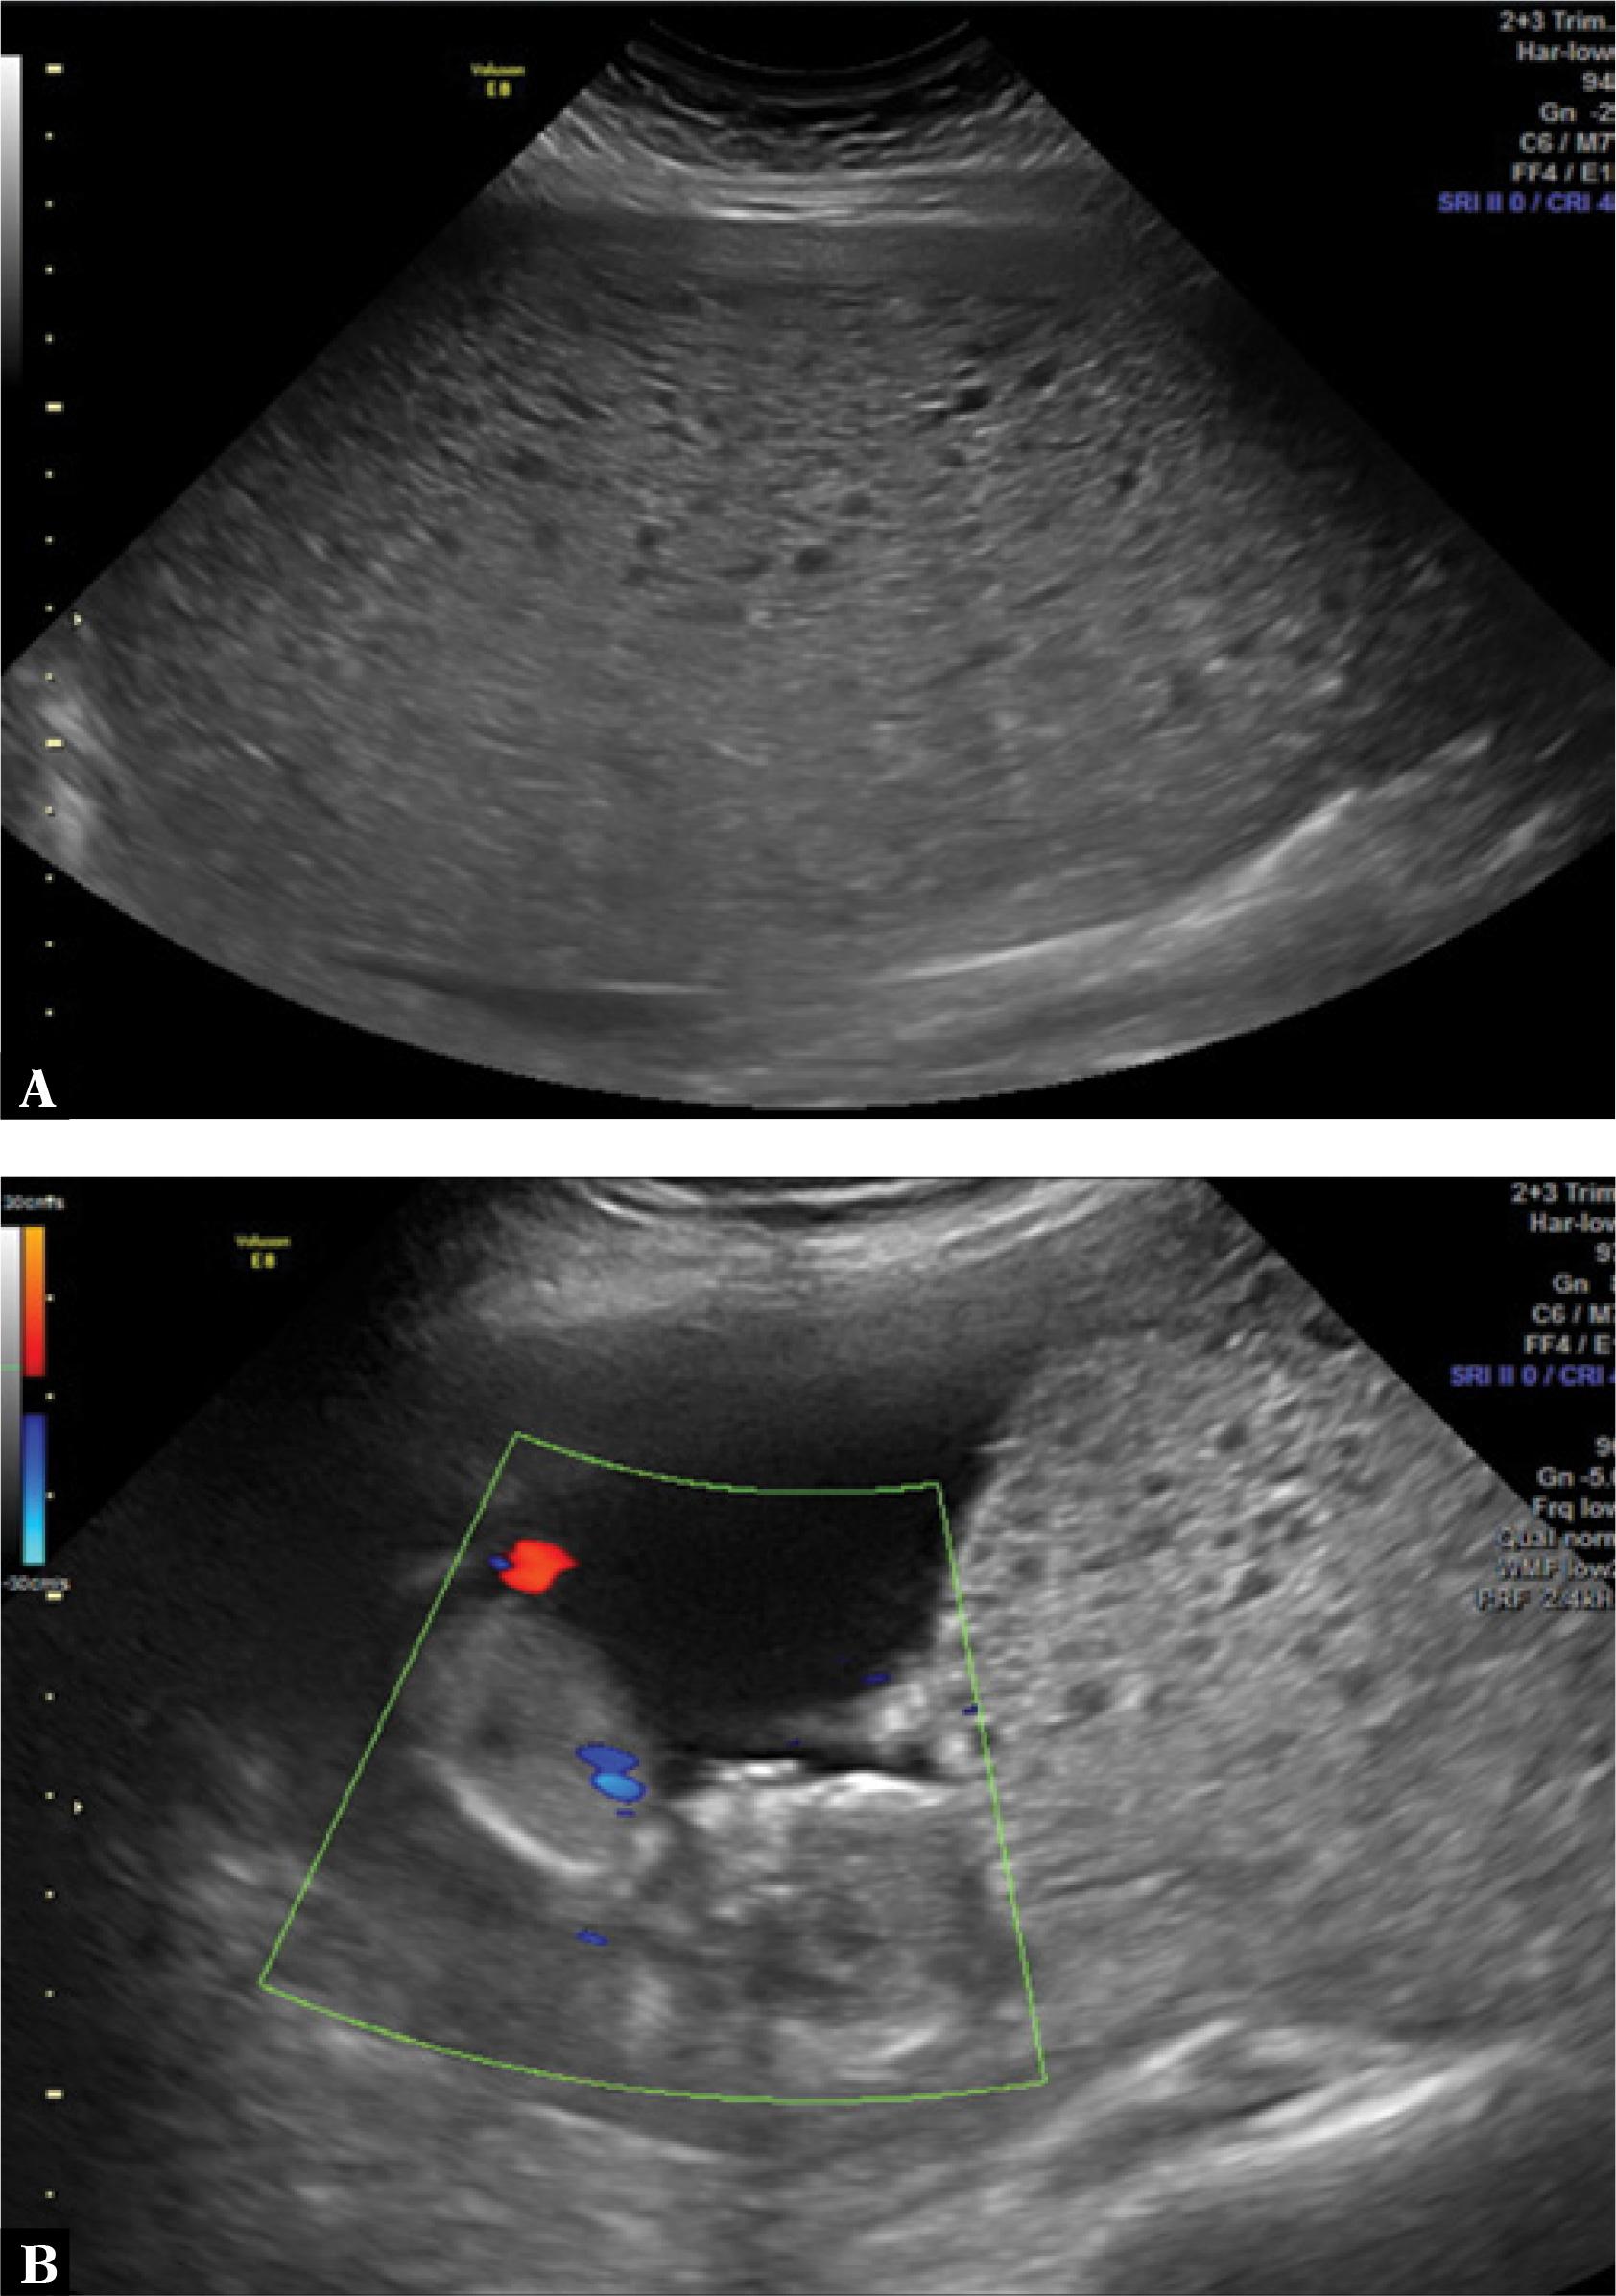

Fig. 1